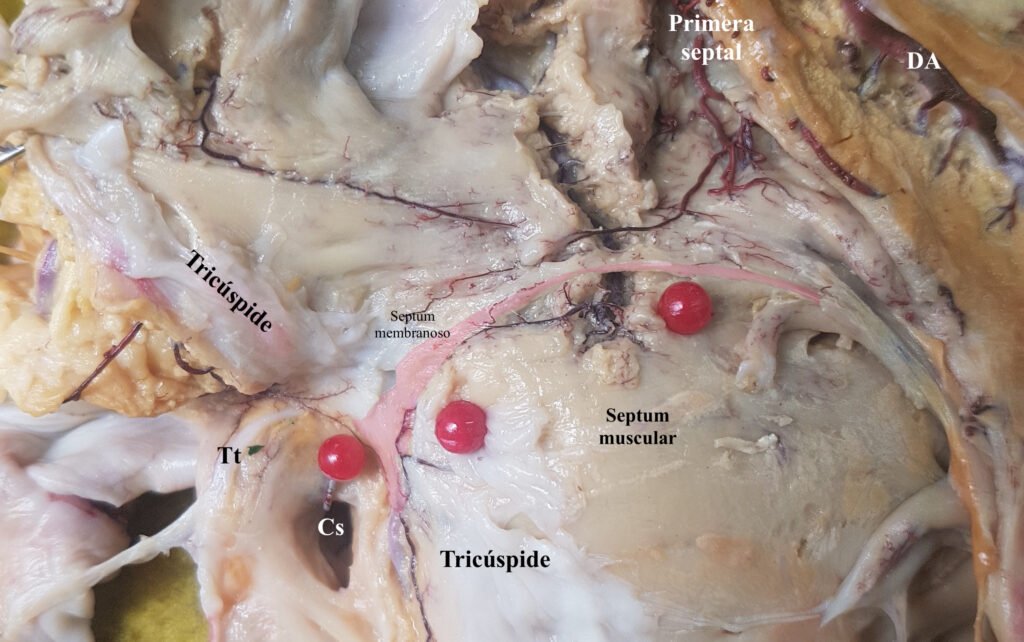

En las siguientes fotografías se ilustran las cuatro fuentes vasculares del nodo atrioventricular.

Dos son conocidas hace décadas, las últimas dos demostradas por nuestro laboratorio hace un par de décadas. Son -estas últimas- la arteria anastomótica auricularis magna o arteria de kugel y la arteria septal derecha.

Ambos vasos se ilustra cómo llegan al sistema de conducción.

La arteria primera septal (1), rama de la descendente anterior (6), se anastomosa con la arteria septal superior derecha (2) rama del origen de la coronaria derecha. Obsérvese cómo se trata de un ramo septal.